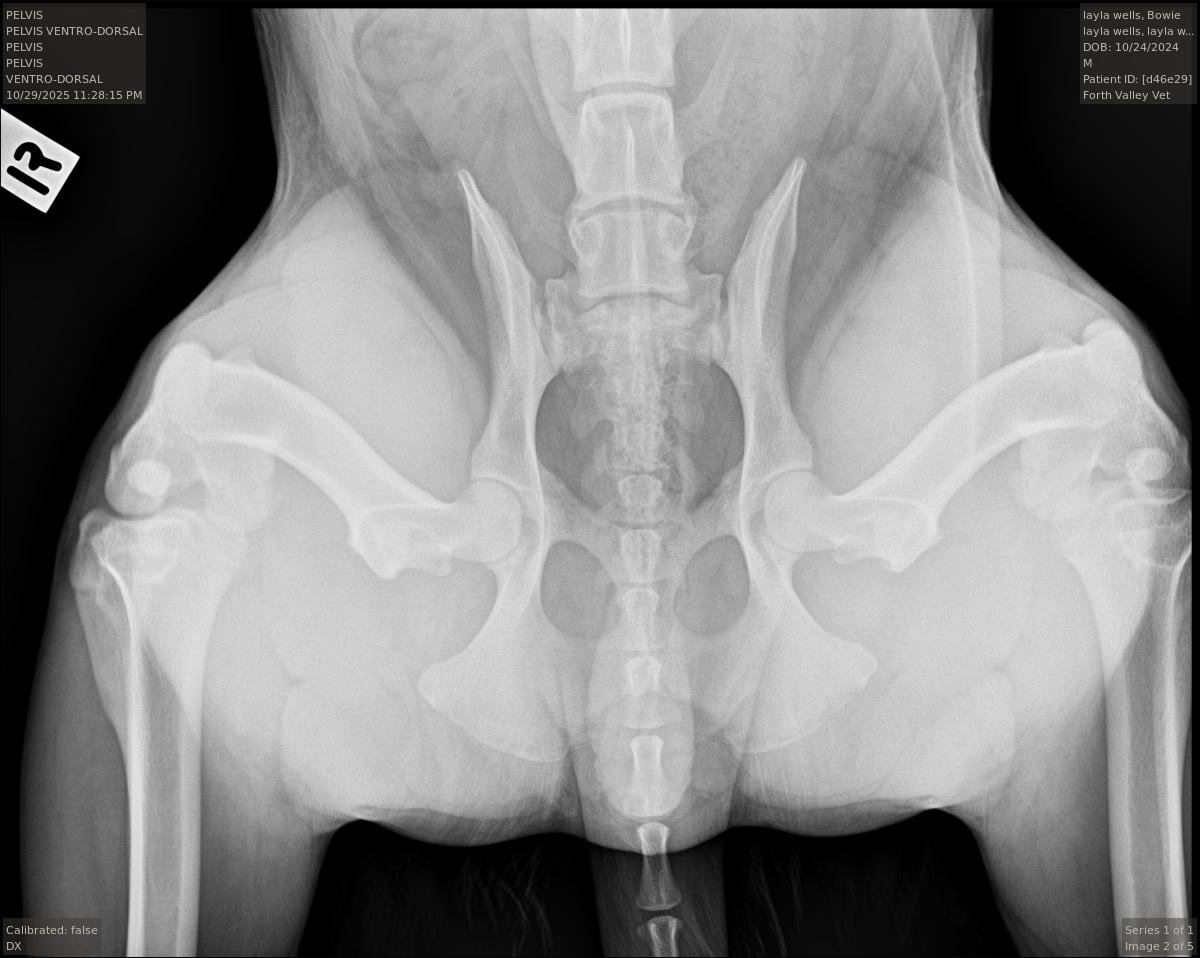

For decades, the industry standard was the "Hip-Extended View." While we still use this view to look for existing arthritis, it has a major flaw when it comes to prediction.

When a dog’s legs are pulled straight back for a traditional X-ray, the joint capsule twists and tightens up.

This can artificially force a loose hip into the socket, making it look "good" on film even if it is loose.

The Traditional Hip-Extended View: To check for any existing osteoarthritis.